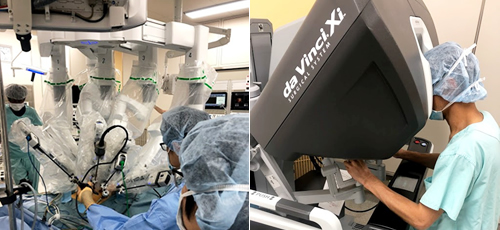

●各臓器の専門家が、腹腔鏡や胸腔鏡、手術支援ロボットを用いた低侵襲治療から多臓器合併切除などの拡大手術まで取り組みます。

きずが小さい手術(低侵襲手術:胸腔鏡・腹腔鏡手術[ロボット支援下手術を含む])を積極的に実施しています。進行がんに対しても安全性が確保できると判断した症例では実施しています。きずが小さいと美容面で有利なだけでなく、早期の回復が期待できます。

また、直腸癌に対しては、術前化学放射線療法を組み合わせることで、治療成績の向上や肛門温存に努めており、2018年4月に保険収載されたロボット支援手術も積極的に取り入れ、常に最新かつ最良の医療を提供することを目標としております。